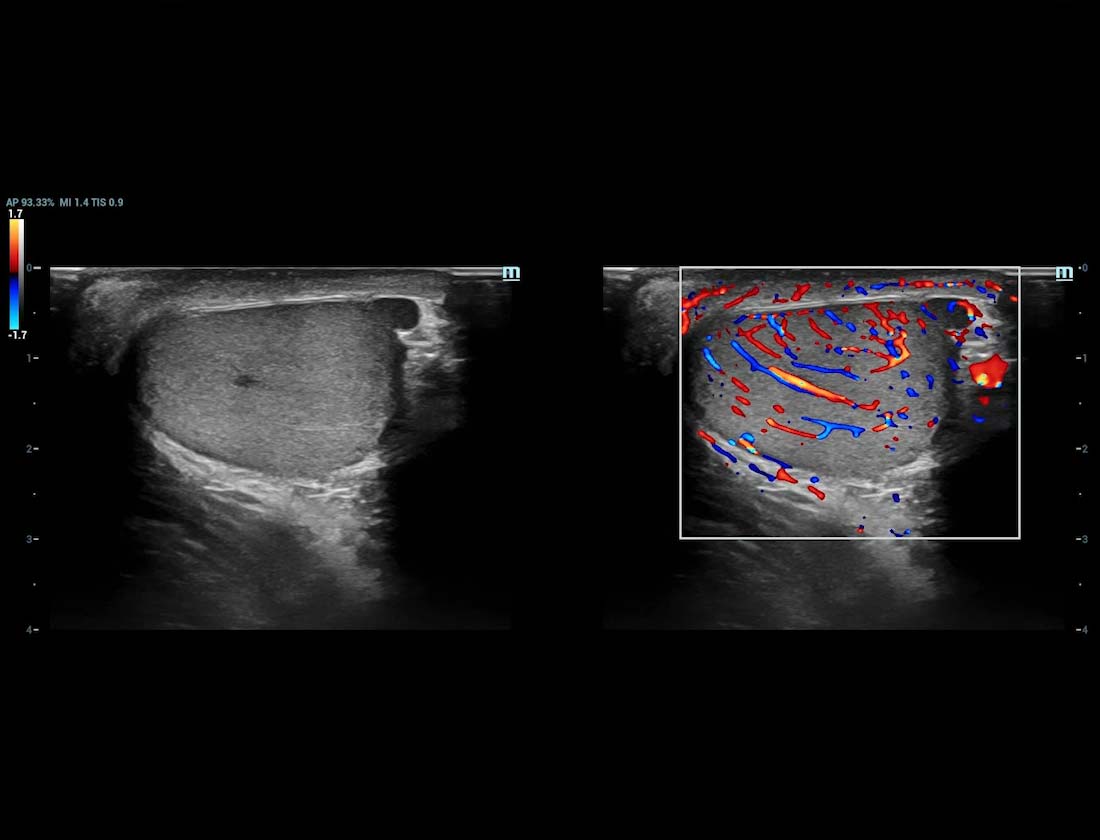

Ultra-Micro-angiografie (UMA)

UMA verbetert het diagnostische vertrouwen door de zichtbaarheid van de bloedstromen uit te breiden tot op het kleinste vaatniveau, met een superieure gevoeligheid en resolutie van de bloedstroom.

Testikel UMA

Varicocele beglazing sUMA